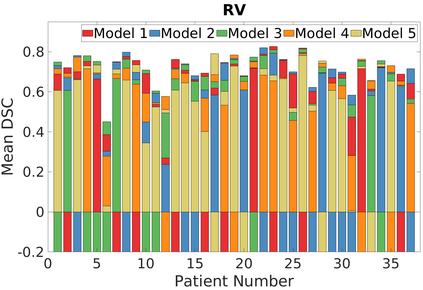

Deep Convolutional Neural Networks (DCNNs) are used extensively in biomedical image segmentation. However, current DCNNs usually use down sampling layers for increasing the receptive field and gaining abstract semantic information. These down sampling layers decrease the spatial dimension of feature maps, which can be detrimental to semantic image segmentation. Atrous convolution is an alternative for the down sampling layer. It increases the receptive field whilst maintains the spatial dimension of feature maps. In this paper, a method for effective atrous rate setting is proposed to achieve the largest and fully-covered receptive field with a minimum number of atrous convolutional layers. Furthermore, different atrous blocks, shortcut connections and normalization methods are explored to select the optimal network structure setting. These lead to a new and full-scale DCNN - Atrous Convolutional Neural Network (ACNN), which incorporates cascaded atrous II-blocks, residual learning and Fine Group Normalization (FGN). Application results of the proposed ACNN to Magnetic Resonance Imaging (MRI) and Computed Tomography (CT) image segmentation demonstrate that the proposed ACNN can achieve comparable segmentation Dice Similarity Coefficients (DSCs) to U-Net, optimized U-Net and hybrid network, but with significantly reduced trainable parameters due to the use of full-scale feature maps and therefore computationally is much more efficient for both the training and inference.